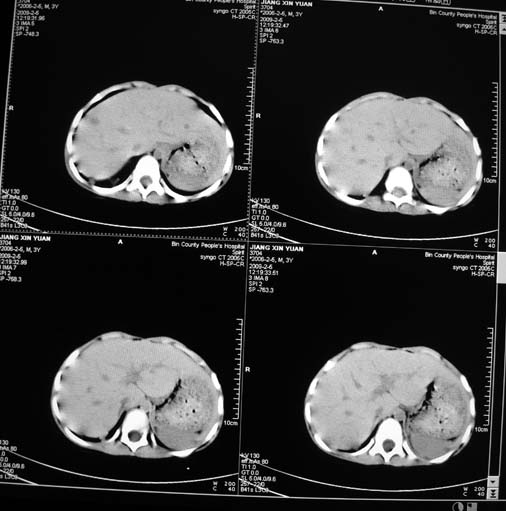

男,3岁,肾母细胞瘤术后,肝脏的低密度是什么?

胰尾下方见两枚囊形灶,肠管?病灶?左侧肾上腺区见团块状影,转移病灶?术后表现?建议与前片对比,肝脏病灶好像有牛眼表现,不除外转移,如果不增强,建议加做个b超,至少可分清其囊性或者实性,又便宜,免费自已给他弄一下也行,对诊断有帮助

左肾母细胞瘤术后,多发性转移可能性大。

左肾母细胞瘤术后:肝脏多发低密度灶,考虑转移可能性大。

左肾母细胞瘤术后:肝脏多发低密度灶,考虑转移可能.请结合临床及增强以及术前检查等